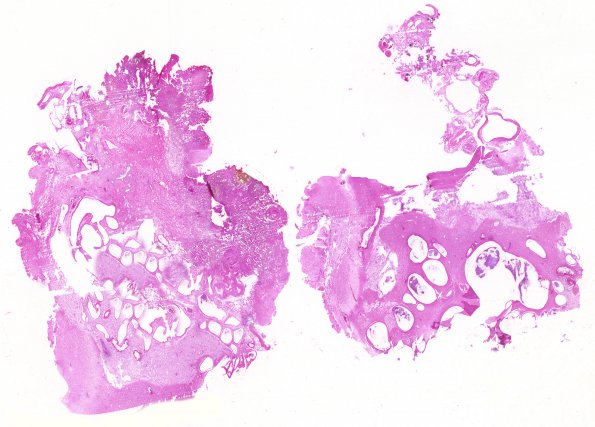

30B1 AVM (Case 30) H&E whole mount

30B1-3 Histologic images of the AVM stained with H&E (30A), trichrome (30B) and elastin (VVG, 30C)